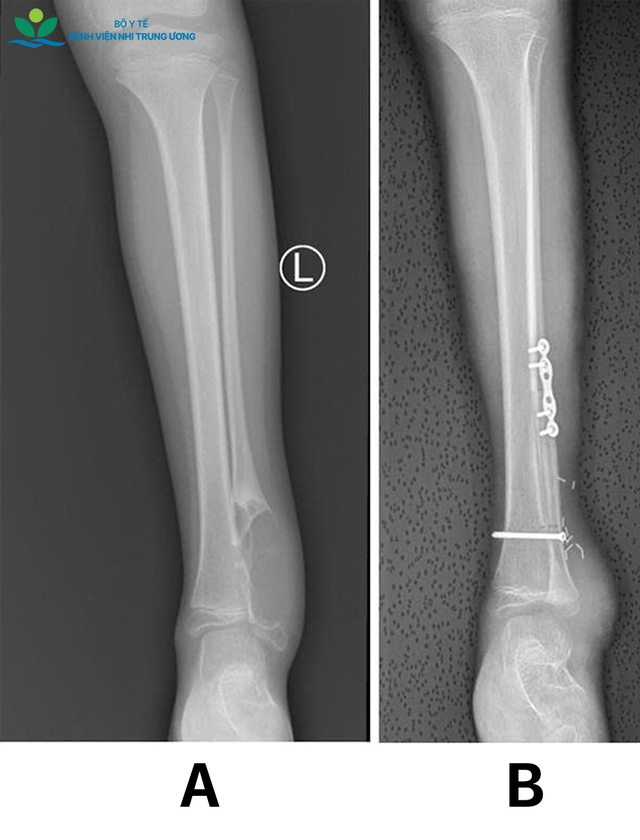

Kết quả thăm khám và chẩn đoán hình ảnh cho thấy khối u Chondrosarcoma (u sụn ác tính) tái phát ở đầu dưới xương mác bên trái (toàn bộ mắt cá ngoài bị tổn thương), kích thước lớn, chèn ép sát các cấu trúc mạch máu và thần kinh quan trọng vùng cổ chân. May mắn, các kiểm tra chuyên sâu xác định bệnh chưa di căn các cơ quan khác. Các bác sĩ đã tiến hành cắt bỏ toàn bộ khối u đầu dưới xương mác trái theo nguyên tắc ung thư xương, giải phẫu bệnh cho kết quả diện cắt âm tính (R0) - điều kiện then chốt để giảm nguy cơ tái phát tại chỗ.

Sau khi hội chẩn kỹ càng giữa các chuyên khoa chỉnh hình, ung thư, chẩn đoán hình ảnh, giải phẫu bệnh,… các bác sĩ đã lựa chọn giải pháp: ghép chỏm xương mác có cuống mạch (vạt xương - vi phẫu), cuống mạch nuôi là động mạch chày trước, kèm đảo da để che phủ phần khuyết da nơi nhận. Ưu điểm của phương pháp này là mang theo hệ mạch nuôi đảm bảo khả năng sống của vạt bao gồm cả xương, sụn, mô mềm, đặc biệt là ở trẻ em cần duy trì tiềm năng tăng trưởng của sụn phát triển ở đầu xương. Đây là ca phẫu thuật tái tạo và bảo tồn chi đặc biệt khó và đầy thách thức với nguy cơ tổn thương các mạch máu và thần kinh, có thể dẫn đến yếu liệt chi sau mổ.

Cứu đôi chân bé gái 8 tuổi khỏi nguy cơ tàn phế vì ung thư sụn- Ảnh 2.